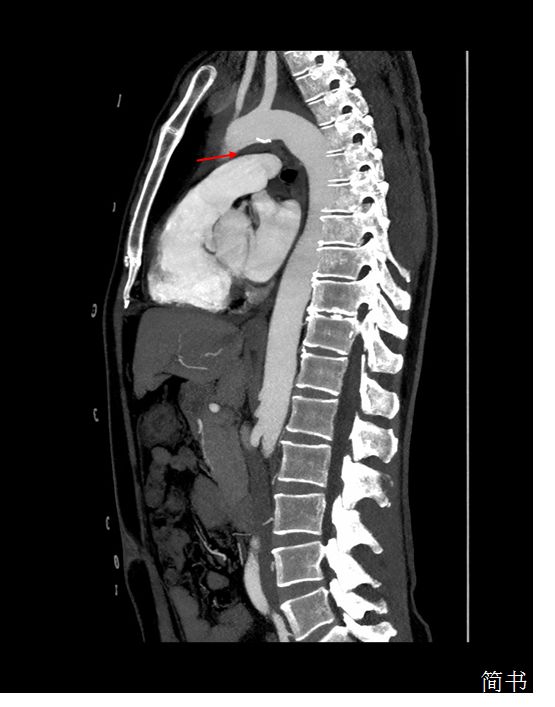

回过头来看我们这位患者,从主动脉CTA矢状位上可以发现主动脉弓与肺动脉间隙被壁内血肿填充(图*箭3**头处),解剖学上左侧喉返神经正好走形在此处,受到主动脉弓血肿压迫导致声带麻痹。至此,拨开疑云见阳光,患者的突发声嘶是由于——继发于主动脉壁内血肿的心脏-声带综合征。

图3 主动脉CTA矢状位:箭头所指部位为主动脉弓与肺动脉间隙,可见该间隙被壁内血肿填充,左侧喉返神经从该间隙环绕主动脉弓后折返向上走形